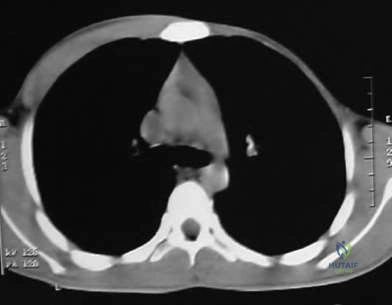

A newborn is diagnosed with a unilateral radial longitudinal deficiency (radial club hand) characterized by an absent radius (Type IV). Before proceeding with any orthopedic interventions, which of the following screening tests is most critical for determining the patient's immediate survival risk?